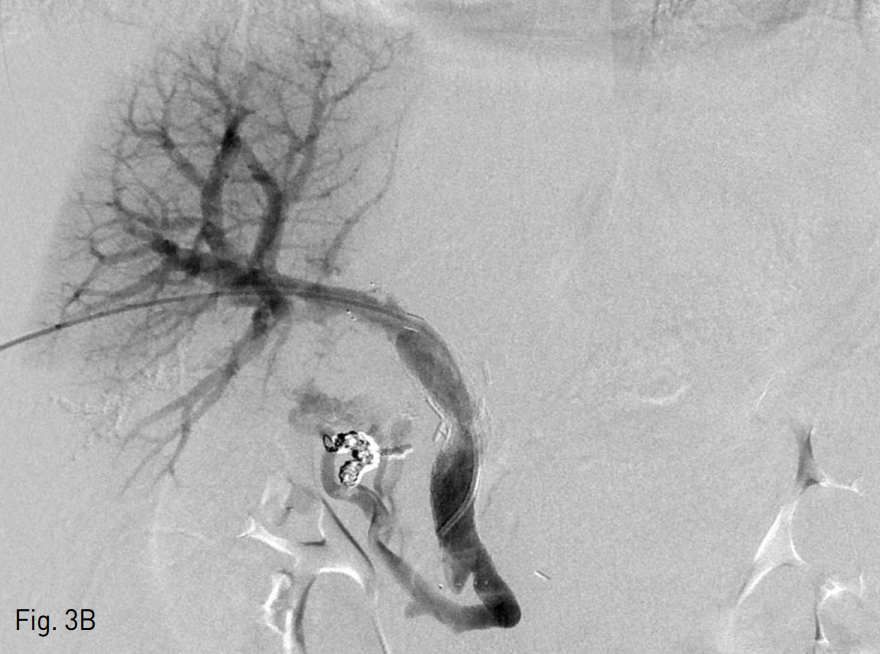

Fig. 2

A. Transhepatic portogram shows filling defect in portal vein (arrows), suggestive of thrombus and extravasation of contrast media (arrowheads) to jejunum.

B. Balloon dilatation, thrombectomy, and stent placement restored portal vein flow and decreased collateral flows.